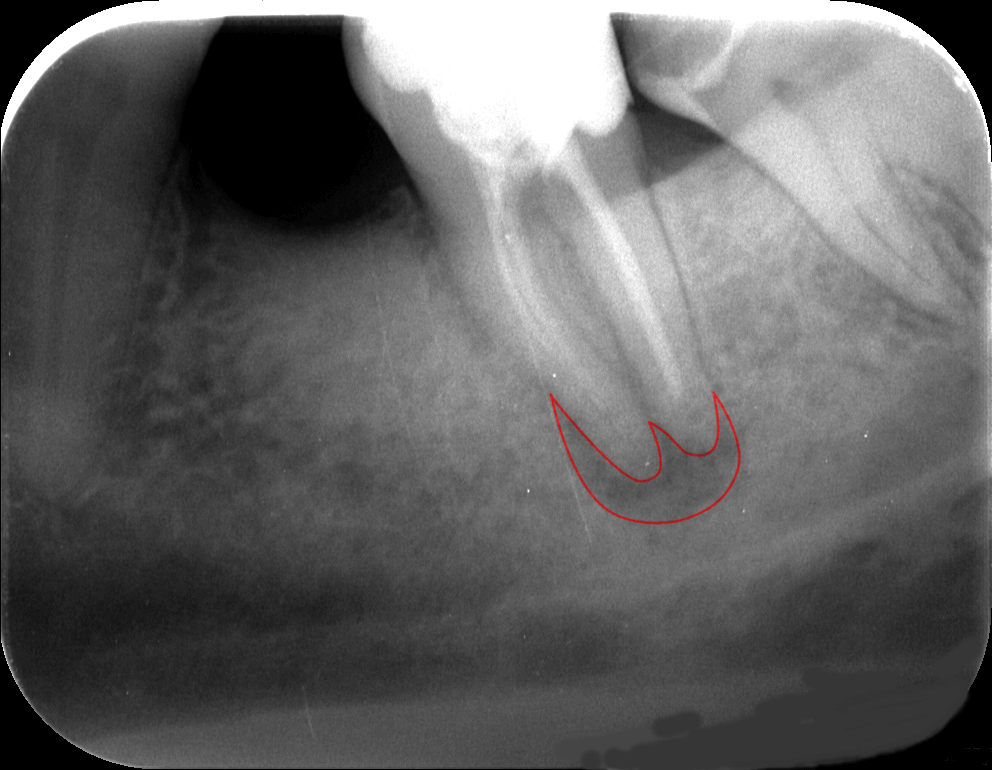

A kiindulási röntgenfelvételen jól látható, hogy a régi gyökértömés minősége nem a legmegfelelőbb, nem sikerült a gyökércsatornákat a teljes hosszon kitisztítani, ezáltal a fog gyökércsúcsa körül gyulladás alakult ki. (Az érintett területet pirossal rajzoltuk körbe.) Sajnos sokszor találkozunk ezzel a problémával. Ami talán még rosszabb, hogy ezek a gyulladások sokszor rejtve maradnak, egészen addig, amíg egyszer csak meg nem fájdul a fog. Ez történt most is, kedves páciensünk igen nagy fájdalmakkal érkezett.

Fog megmentése mikroszkópos kezeléssel kiindulási állapot